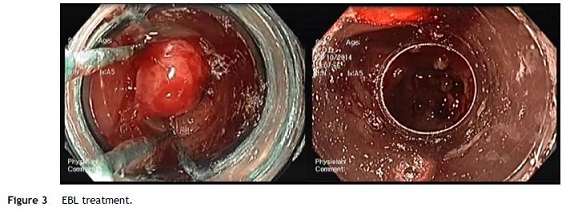

Nevertheless the patient presented with a new episode of symptomatic anemia, and an hemoglobin level of 3.7 g/dL was observed. After transfusion of red blood cells an OGD was performed. At that time, since GAVE persisted despite treatment sessions using APC, and taking into consideration the severity and short recurrence intervals of symptomatic anemia, a decision was made to perform EBL (multi-band ligator, Ezy Shoot, G-Flex®). Six bands were applied, starting from lesions adjacent to the pylorus, then continued proximally in the antrum until most of the GAVE affected areas were treated (Fig. 3). No complications of the procedure were reported, and the patient was discharged after 24 h, maintaining propranolol and pantoprazole. Endoscopic evaluation was performed every 4 weeks and another 3 sessions of EBL were performed with almost complete eradication of GAVE (Fig. 4). Following the first EBL treatment the patient remained asymptomatic with stable hemoglobin level of 12 g/dL and no need of red cells blood transfusion or iron supplementation.

EBL is widely employed as an effective treatment for esophageal varices because of its capacity to obliterate submucosal varices. With respect to GAVE, since the histological changes are present in the mucosa and submucosal layer, EBL may be more effective because of its ability to obliterate the submucosal vascular plexus.10 In this patient, the presence of extensive areas of the antrum affected with a high-density of both mucosal and submucosal vascular malformations is a likely explanation for the primary failure of the APC treatment. Given the fast recurrence of severe anemia, often within 4 weeks, the decision to perform EBL yielded positive results, with eradication of GAVE with 4 sessions of EBL with no complications, namely abdominal pain.